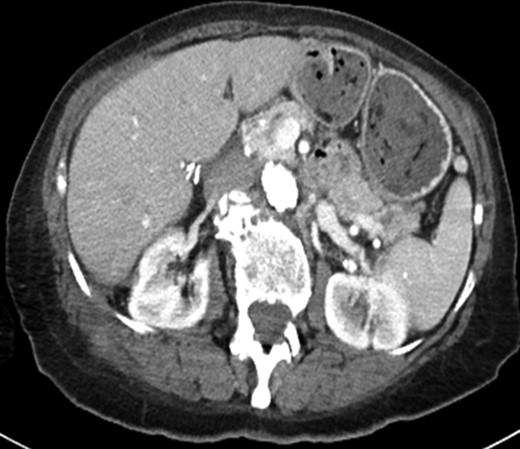

(a) Axial image of the CT of the abdomen with IV contrast, demonstrating a complex partially cystic, partially solid enhancing mass abutting the right hepatic lobe and right kidney and extending into the abdominal wall. (b) Axial T2-weighted sequence of the abdomen (axial T2 Single Shot Fast Spin Echo) showing the cystic component of the mass involving the right retroperitoneal space. (c) Axial T1-weighted fat saturation post-contrast sequence of the abdomen (axial T1 Liver Acquisition with Volume Acquisition after the intravenous administration of gadolinium) demonstrating enhancement of the solid component of the mass extending to the right flank musculature. (d) PET/CT showing increased FDG activity at the solid component identified on CT and MRI within the right flank musculature.

MRI confirmed the presence of a complex, partially cystic mass (Fig. 1b). The solid enhancing component extended into the right flank musculature as well as 11th and 12th ribs (Fig. 1c). Image-guided core biopsy revealed atypical spindle cells (Fig. 2a). The pathologic impression was spindle cell neoplasm, favor STS. Immunohistochemical staining revealed high Ki-67 (25%) and positive vimentin.